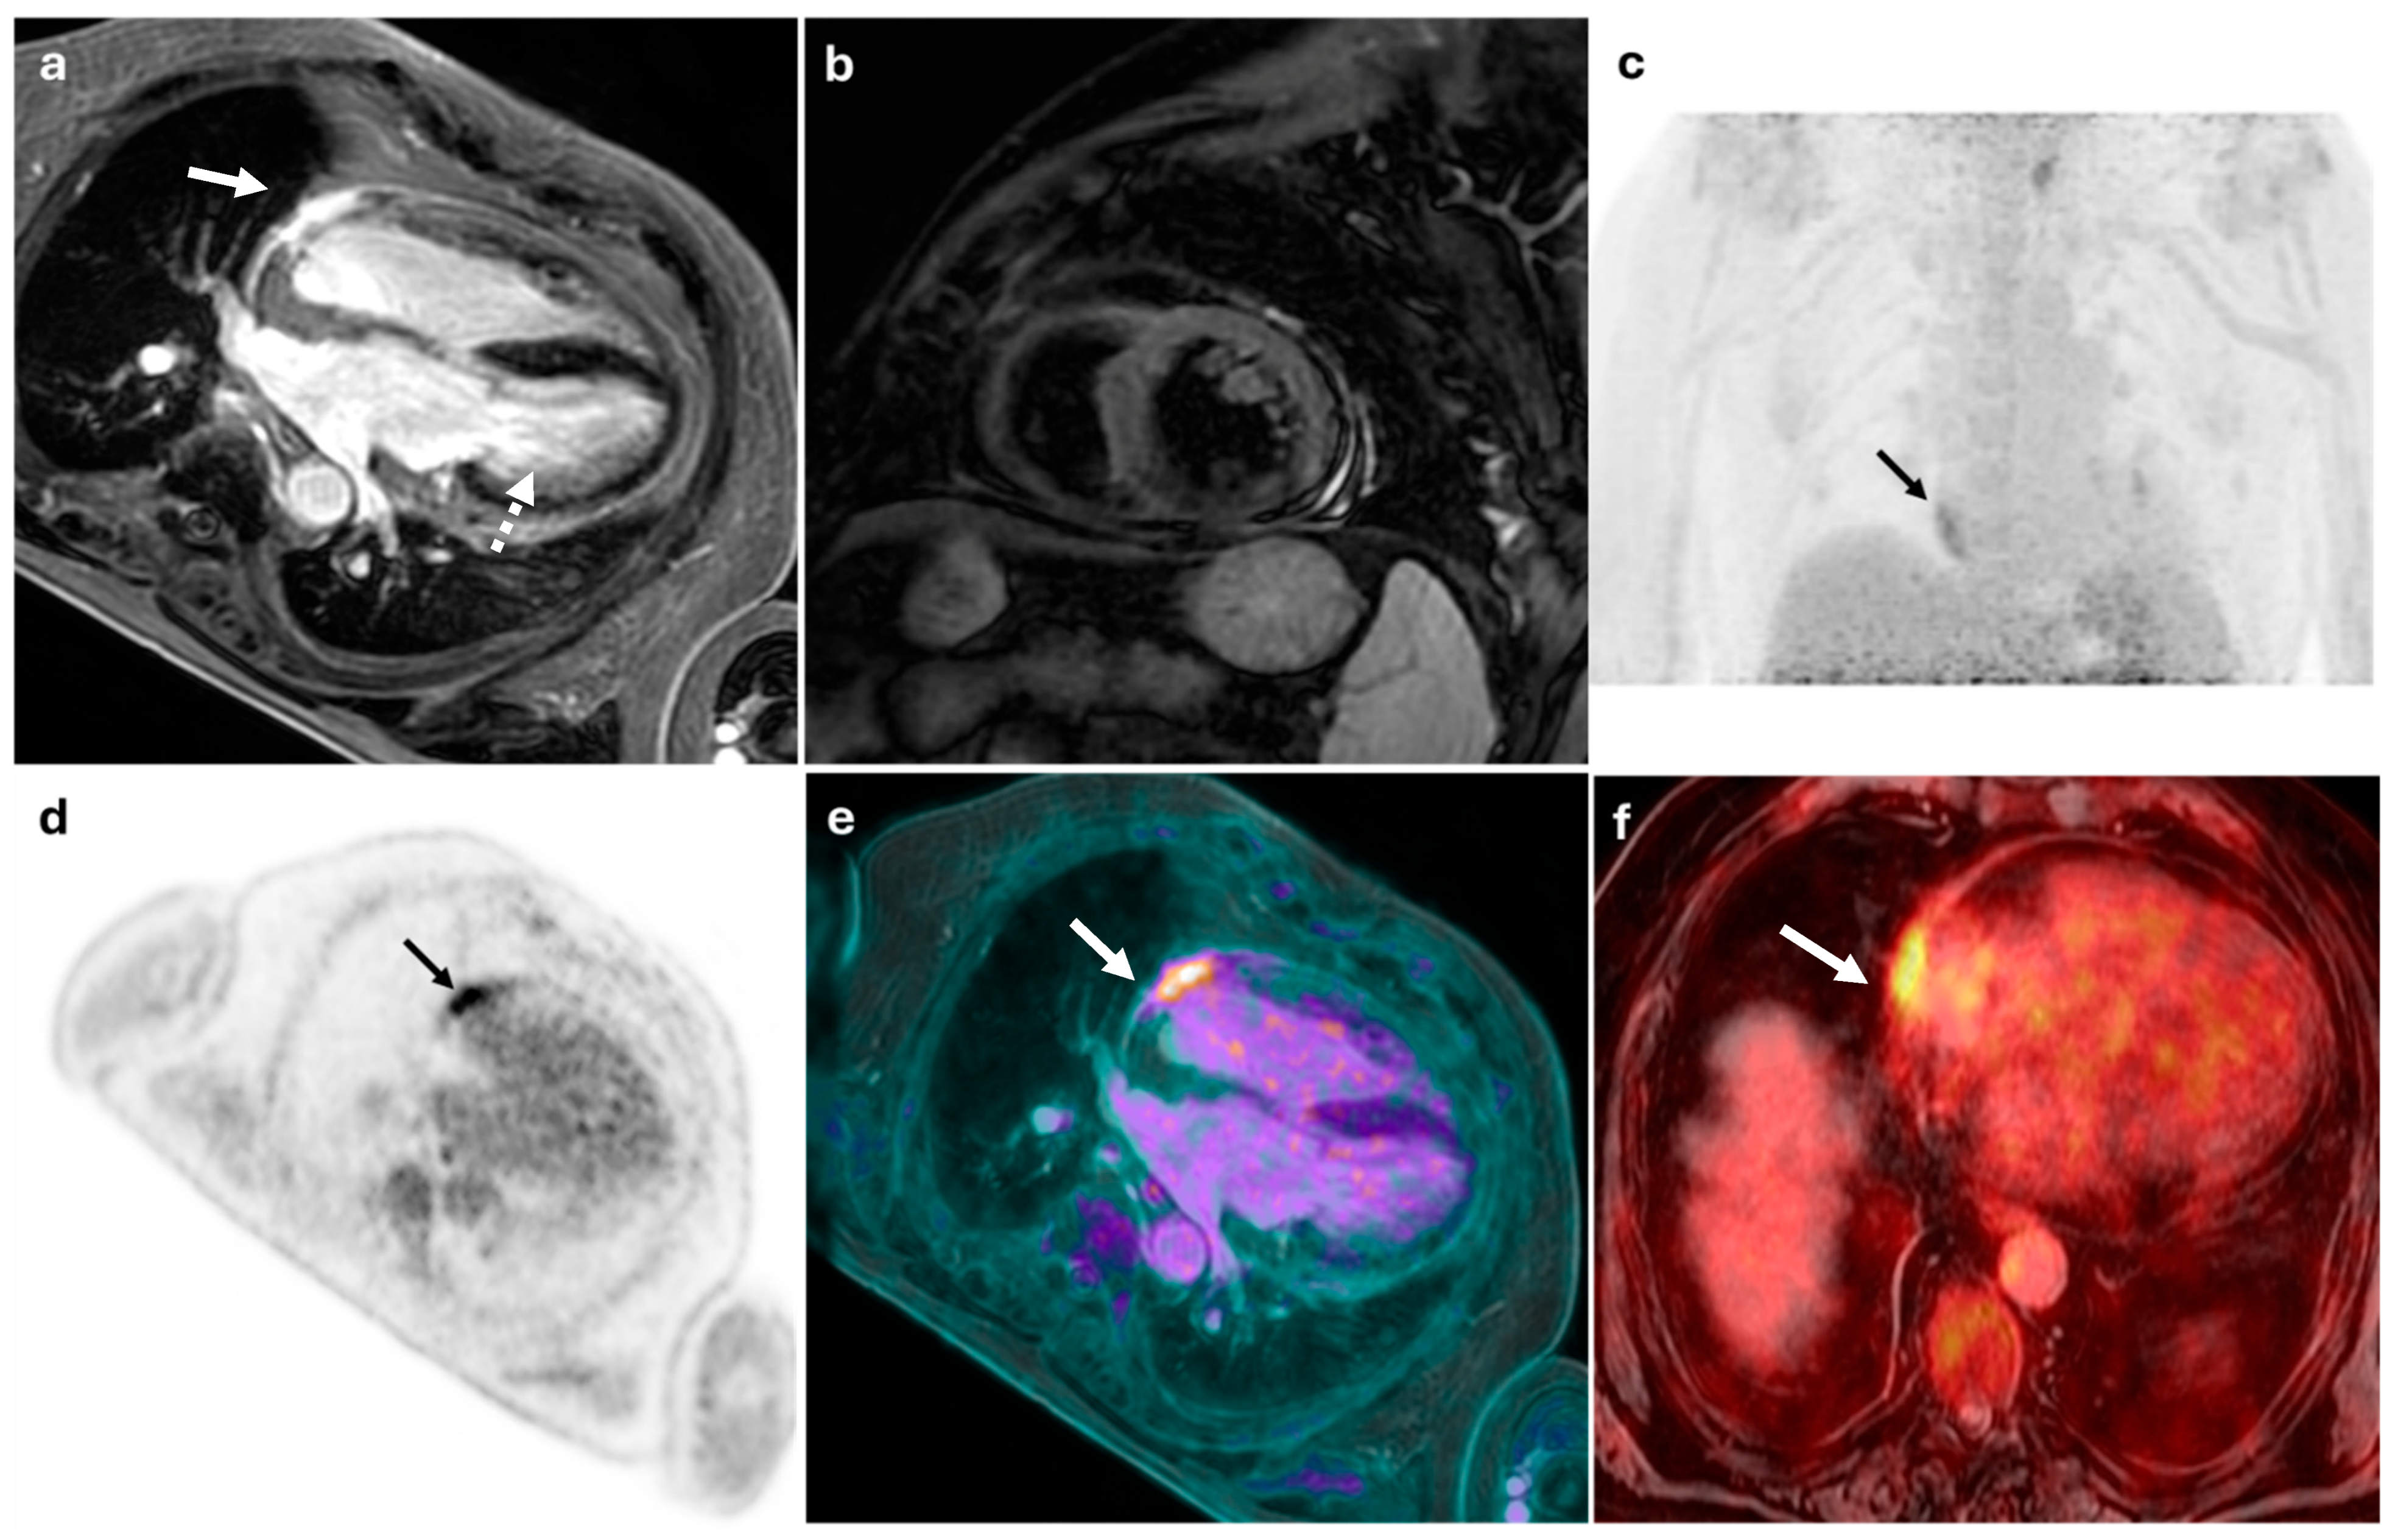

Figure 3.

56-year-old male with suspected myopericarditis. (a) displays an MRI image showing epicardial late gadolinium enhancement localized to the mid-basal inferolateral wall of the left ventricle (white dashed arrow) and the anterolateral wall of the right ventricle (white arrow), without evidence of myocardial edema (b). (c,d) show FDG-PET images with pathological focal glucose hyperaccumulation in the pericardium at the anterolateral aspect of the heart (SUVmax: 5), although precise anatomical localization was inconclusive (black arrows). The combined PET/MRI findings were conclusive for right ventricular myopericarditis (white arrows) (e,f).